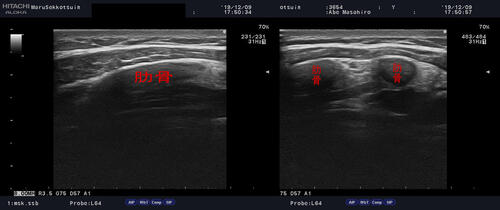

触診にて圧痛点を確認し、患部の状態をエコーで確認。

明確な骨折等の反応は無かったですが、

ここ最近、風邪等で咳・くしゃみの繰返しによって、

肋骨及び肋軟骨を傷められる方が大変多いです。